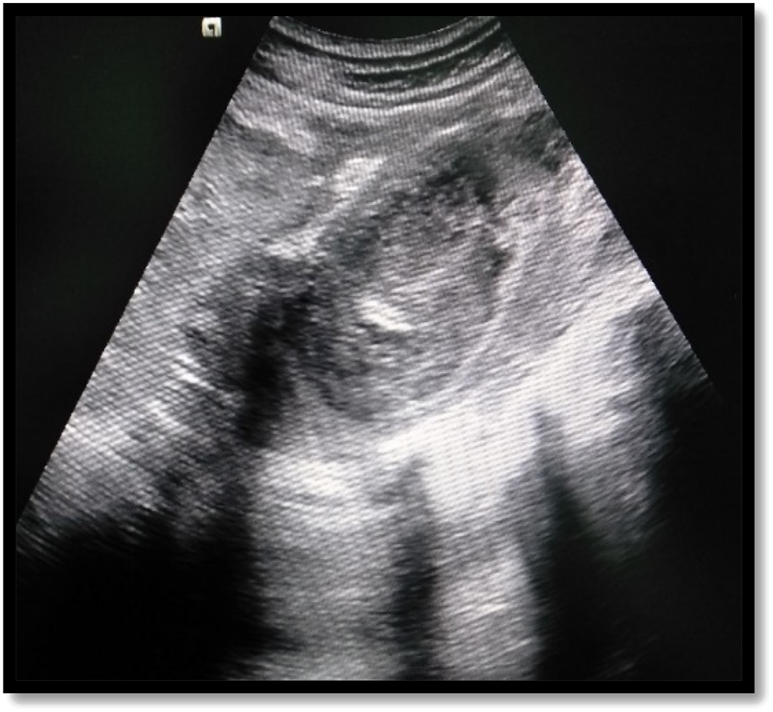

US was done in all cases of IPA, but was diagnostic in 27 (84.4%) patients (Figure 1). CT was done in 28 (87.5%) patients and MRI in 3 (9.4%) for further characterisation of abscess and underlying cause (Figure 2). Eighteen (56.3%) patients had primary IPAs without causal origin, and 14 (43.7%) had secondary IPAs (Table 2). The most common cause of secondary IPA was spinal tuberculosis 7 (21.9%). Right-sided unilateral involvement was the most common presentation in 16 (50%) cases with 12 (37.5%) cases involving left side and 4 (12.5%) cases having bilateral iliopsoas abscess. Multiple IPAs were found in 5 (15.6%). The estimated mean Volume of abscess on US was 114.1 ± 92.9 mL (range, 30–410 mL) (Table 2).

Ultrasonographic image shows heteroechoic collection in the psoas muscle.